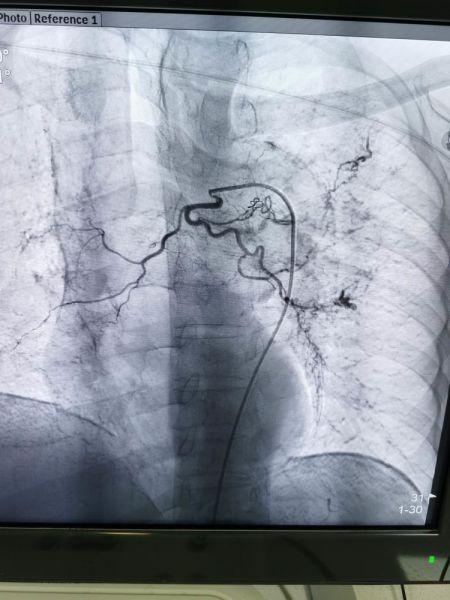

杨某反复咯血十余天,于元月23日住院,入院诊断:肺炎并咯血,结核?高血压病,二型糖尿病。大年三十下午三点三十分急诊手术,DSA示:右上支气管动脉发现多个出血灶。

栓塞后病灶出血停止

左下支气管动脉发现多个出血灶

左上支气管动脉与出血病灶动脉交通

用栓塞微粒球+PVA+弹簧圈三明治方法栓塞满意,手术历时一小时四十分钟,共栓塞三支犯罪血管,元月31日康复出院。